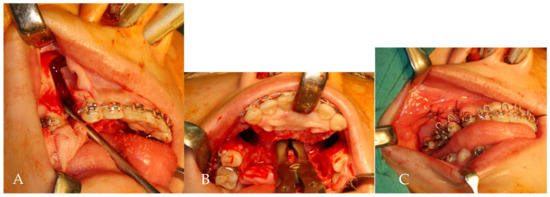

Modified AMSO was performed by making a vertical releasing incision from the posterior to distal interdental papilla of the first premolar, extending to the vestibular depth (Figure 2A). The mucoperiosteal flap was raised from 5 mm above the apex of the first premolar to the lateral rim of the piriform aperture using a subperiosteal tunneling technique. A vertical incision was made through the mucoperiosteum overlying the anterior nasal spine (ANS) and extended 5 mm inferiorly (Figure 2B). Through subperiosteal tunneling beneath the ANS, the mucoperiosteal flaps overlying the medial rim of the piriform aperture and nasal floor were reflected. An arching palatal incision was made from the anterior to the medial interdental papilla of the first premolar and continued to the contralateral side. The palatal flap was reflected posteriorly to the first molar area. Under protection of nasal mucosa, subapical osteotomy (5 mm above tooth apex) and bone removal were performed in the region of extracted tooth and then oblique to infero-lateral portion of piriform aperture (Figure 3A).

Figure 2.

(A) Vestibular incision of modified AMSO: a vertical releasing incision from the posterior to distal interdental papilla of the first premolar, extending to the vestibular depth. (B) A vertical incision is made through the mucoperiosteum overlying the anterior nasal spine and carried inferiorly 5 mm.

Figure 3.

(A) Buccal ostectomy of lateral maxilla through retracted wound margins. (B) An anterior curving transpalatal ostectomy was performed to connect bilateral buccal ostectomy sites. A rongeur forcep was used to remove a small portion of nasal septum. (C) A predetermined palatal acrylic splint fixed with anterior and posterior teeth by circumdental wires.

Under direct vision, an anterior curving transpalatal ostectomy was performed to connect bilateral buccal ostectomy sites (Figure 3B). A small portion of nasal septum was removed by rongeur forcep. Subsequently, the anterior maxillary segment was passively placed into a predetermined palatal acrylic splint and fixed with posterior teeth by circumdental wiring (Figure 3C). No maxillary intersegmental fixation or maxillomandibular fixation was involved. The palatal splint was removed 6 weeks postoperatively.